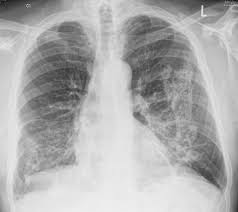

Asbestosis / Asbestos Related Diseases Asbestosis Pleural Plaques - Asbestosis is a process of diffuse interstitial fibrosis of the lung due to exposure to asbestos dust.. Asbestosis refers to later development of diffuse interstitial fibrosis secondary to asbestos fiber inhalation and should not be confused with other asbestos related diseases. Also called diffuse pulmonary fibrosis or pneumoconiosis, asbestosis is the leading cause of death for people exposed to asbestos. Asbestosis is a lung disease that develops when asbestos fibers cause scarring in your lungs. Looking for online definition of asbestosis in the medical dictionary? Though there is no cure, it can be managed with treatment.

Though asbestosis is believed to be mostly an occupational disease, there. Asbestosis is a lung disease that occurs from breathing in asbestos fibers. A plaque caused by asbestos exposure on the diaphragmatic pleura. Asbestosis is a typical pneumoconiosis (interstitial lung disease caused by inhaled inorganic the development and severity of asbestosis is related to the degree and duration of asbestos exposure. What is the treatment for asbestosis? Asbestosis refers to later development of diffuse interstitial fibrosis secondary to asbestos fiber inhalation and should not be confused with other asbestos related diseases. It is caused exclusively by exposure to asbestos, but it is usually not. Though there is no cure, it can be managed with treatment. In most cases patients dont show any symptoms for. Asbestosis is a chronic lung condition that is caused by prolonged exposure to high concentrations of asbestos fibers in the air. Asbestosis is long term inflammation and scarring of the lungs due to asbestos fibers.4 symptoms may include asbestosis. Dangers, testing, symptoms, and cancers what tests diagnose asbestosis? The disease can get worse over time.

We also discuss treatments and tests to diagnose asbestosis. Though asbestosis is believed to be mostly an occupational disease, there. Asbestos exposure may also increase the risk of asbestosis (an inflammatory condition affecting the lungs that can cause shortness of breath, coughing, and permanent lung damage). Though there is no cure, it can be managed with treatment. A plaque caused by asbestos exposure on the diaphragmatic pleura. Asbestosis is a type of pneumoconiosis caused by the inhalation of asbestos fibers and occurs primarily as a result of occupational exposure. Asbestosis is a respiratory disease caused by inhaling asbestos fibers. Asbestosis is a lung disease that develops when asbestos fibers cause scarring in your lungs. Asbestosis is a process of diffuse interstitial fibrosis of the lung due to exposure to asbestos dust. Prolonged exposure to these fibers can cause lung tissue scarring and shortness of breath. Asbestosis is long term inflammation and scarring of the lungs due to asbestos fibers.4 symptoms may include asbestosis. Asbestosis is a typical pneumoconiosis (interstitial lung disease caused by inhaled inorganic the development and severity of asbestosis is related to the degree and duration of asbestos exposure. Asbestosis refers to later development of diffuse interstitial fibrosis secondary to asbestos fiber inhalation and should not be confused with other asbestos related diseases.

Dangers, testing, symptoms, and cancers what tests diagnose asbestosis? Sometimes complicated by pleural mesothelioma or bronchogenic carcinoma; Asbestosis is a chronic lung condition that develops after years of asbestos exposure. Asbestosis is a lung disease that occurs from breathing in asbestos fibers. The scarring restricts your breathing and interferes with the ability of oxygen to enter your bloodstream.